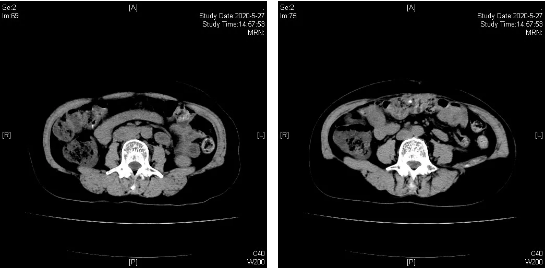

治疗前(2019.07.09)

治疗后(2020.05.27)

入科时,患者营养状态PG-SGA法评估为C级,双侧小腿腓肠肌弹性明显下降体积萎缩,显著的肠道功能障碍症状和体征:腹胀、恶心、呕吐,几乎不能经口进食。经积极采用减轻肠壁水肿、减少肠液分泌等机械性肠梗阻内科常规处置方法,同时联合肠外营养支持和代谢调理治疗、腹腔穿刺置管引流腹水等治疗方法,患者腹胀迅速得以明显好转,肛门开始通气通便,进食也明显改善,8-5日拔出了先前放置的小肠减压管。期间,基因检测示BRCA1突变型。在营养支持和代谢调理治疗的护驾下,8-19至11-13患者顺利完成“紫杉醇+卡铂”方案化疗共计5周期。期间,9-30日、11-11日的CT评估均显示腹腔腹膜病灶较前进一步缩小。由于患者已行6周期TC化疗,同时患者BRCA1基因突变,后予奥拉帕利 300mg bid口服靶向维持治疗至今,目前CA125正常,期间于2020-5-27、2020-7-14 CT扫描评效,均显示SD缩小。